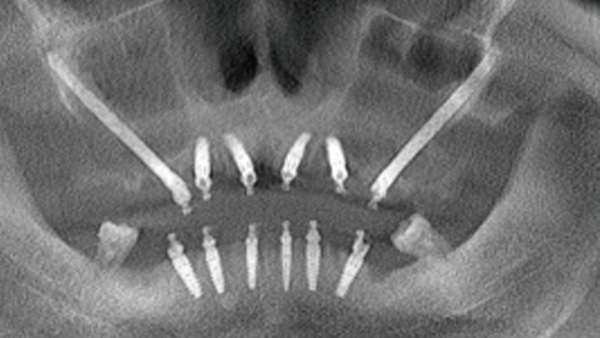

覆蓋所有牙位、即刻種植、即拔即種、全口無牙頜種植